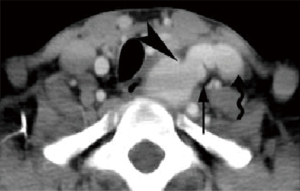

Vascular masses originating from the carotid space are rare, varying from aneurysm, pseudo-aneurysm, to carotid dissection, atherosclerosis, thrombus in the ICA or IJV, and fibromuscular dysplasia, which are identifiable on both MRI/magnetic resonance angiography (MRA) and CT/CTA (35-37). ICA aneurysm, usually arising from atherosclerotic ICA, is identified by their intimate relationship and synchronous enhancement with the ICA on CT or MR imaging (Figure 14). Pseudoaneurysms are often secondary to neck trauma and result from partial to complete disruption of the vascular wall, ultimately leading to hemorrhage contained by the adventitia of the vessel wall or perivascular soft tissues (Figure 15) (36). Neck AVF is usually a result of trauma which causes partial transaction of an adjacent artery and vein. AVF tends to be more clinically apparent. Contrast-enhanced CT may show direct communication between and synchronous of the artery and vein (Figure 16).